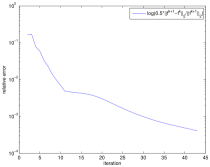

Quantitative assessments of the reconstruction quality of these methods are given in Table 5, where the relative errors, SSIM values and computation time are presented. Although Algorithm 1 that solves the re-weighted JSR model is relatively time consuming, we are able to gain on quality of the reconstructed images. Finally, to numerically demonstrate the convergence of the Algorithm 1, we present the decay of , and the cost function of the re-weighted JSR model in Figure 9(a), 9(b) and 9(c) respectively.